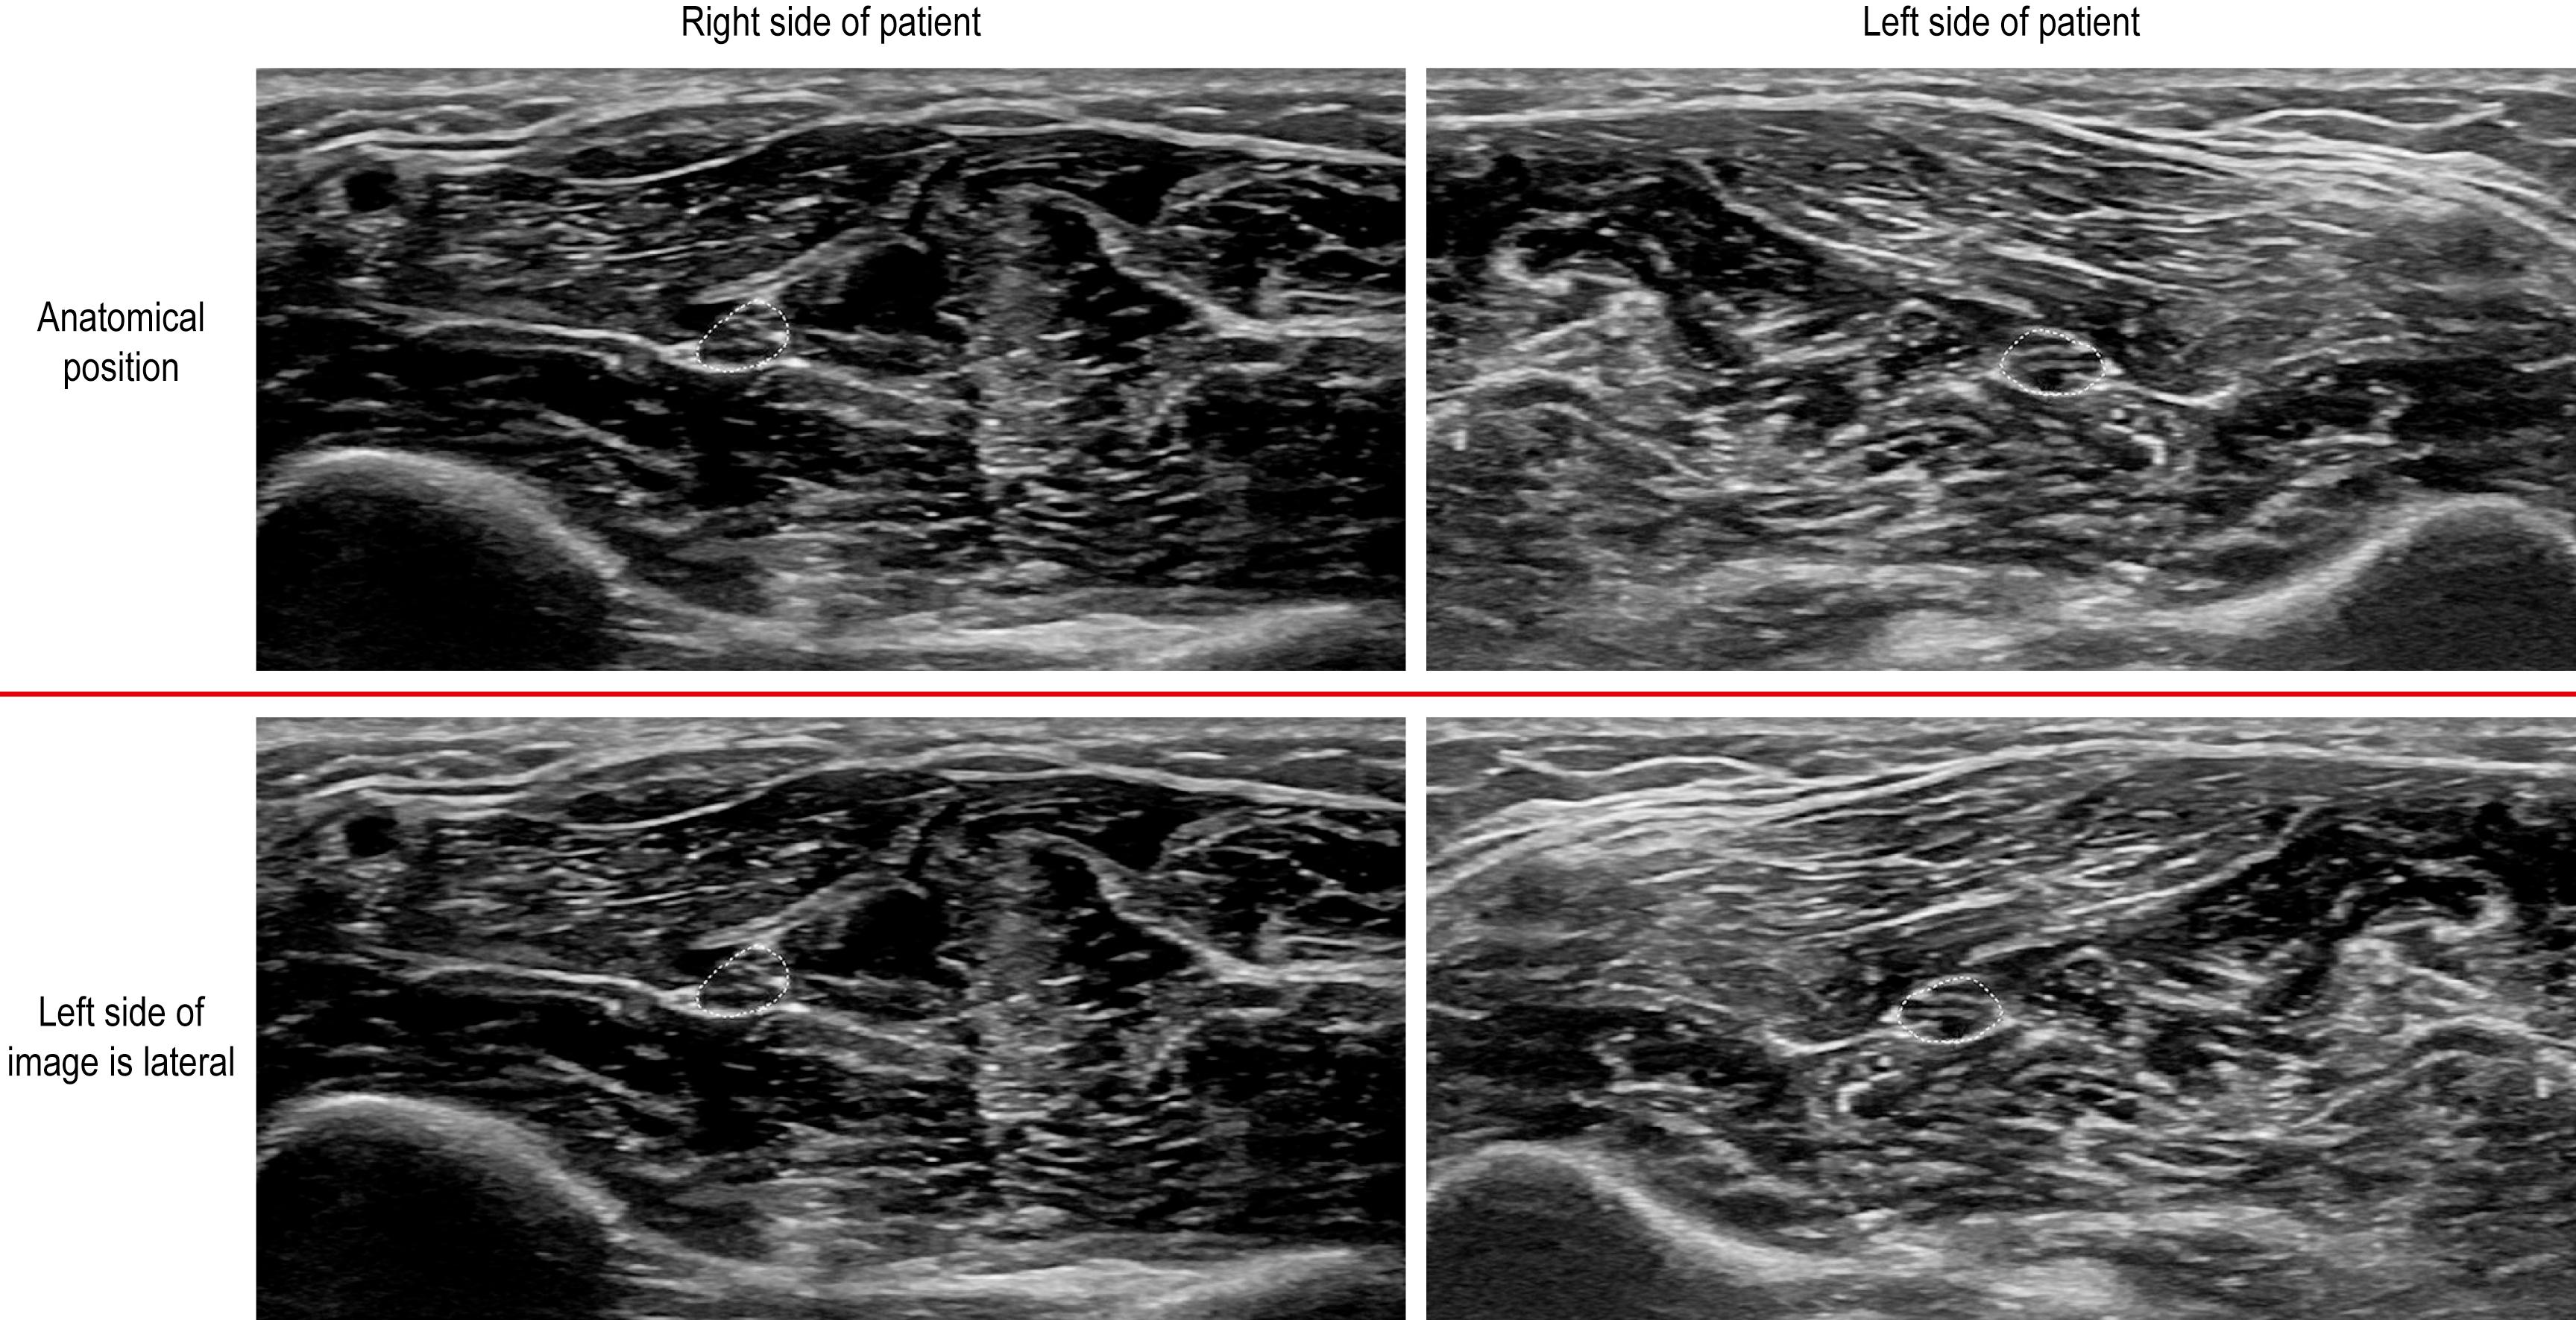

Next, the proper orientation of the images must be maintained. Every ultrasound probe has some type of ridge, button, or symbol on one end of the probe that corresponds to the upper left of the display screen. By convention, when doing a longitudinal study, the left of the screen should always be facing cephalad. When obtaining an axial image, by common convention, the left side of the screen corresponds to the right side of the patient, similar to the convention for magnetic resonance imaging (MRI) and computerized tomography scans (i.e., the anatomic position). Using this approach, the image orientation results in mirror images comparing the left with the right side ( Fig. 17.14 , top image). However, an alternative is to have the left side of the screen always facing the patient’s lateral side. When using this approach, comparing one side to the other, the orientation will remain the same for both left and right ( Fig. 17.14 , bottom image).

Fig. 17.14, Conventions for axial scans.